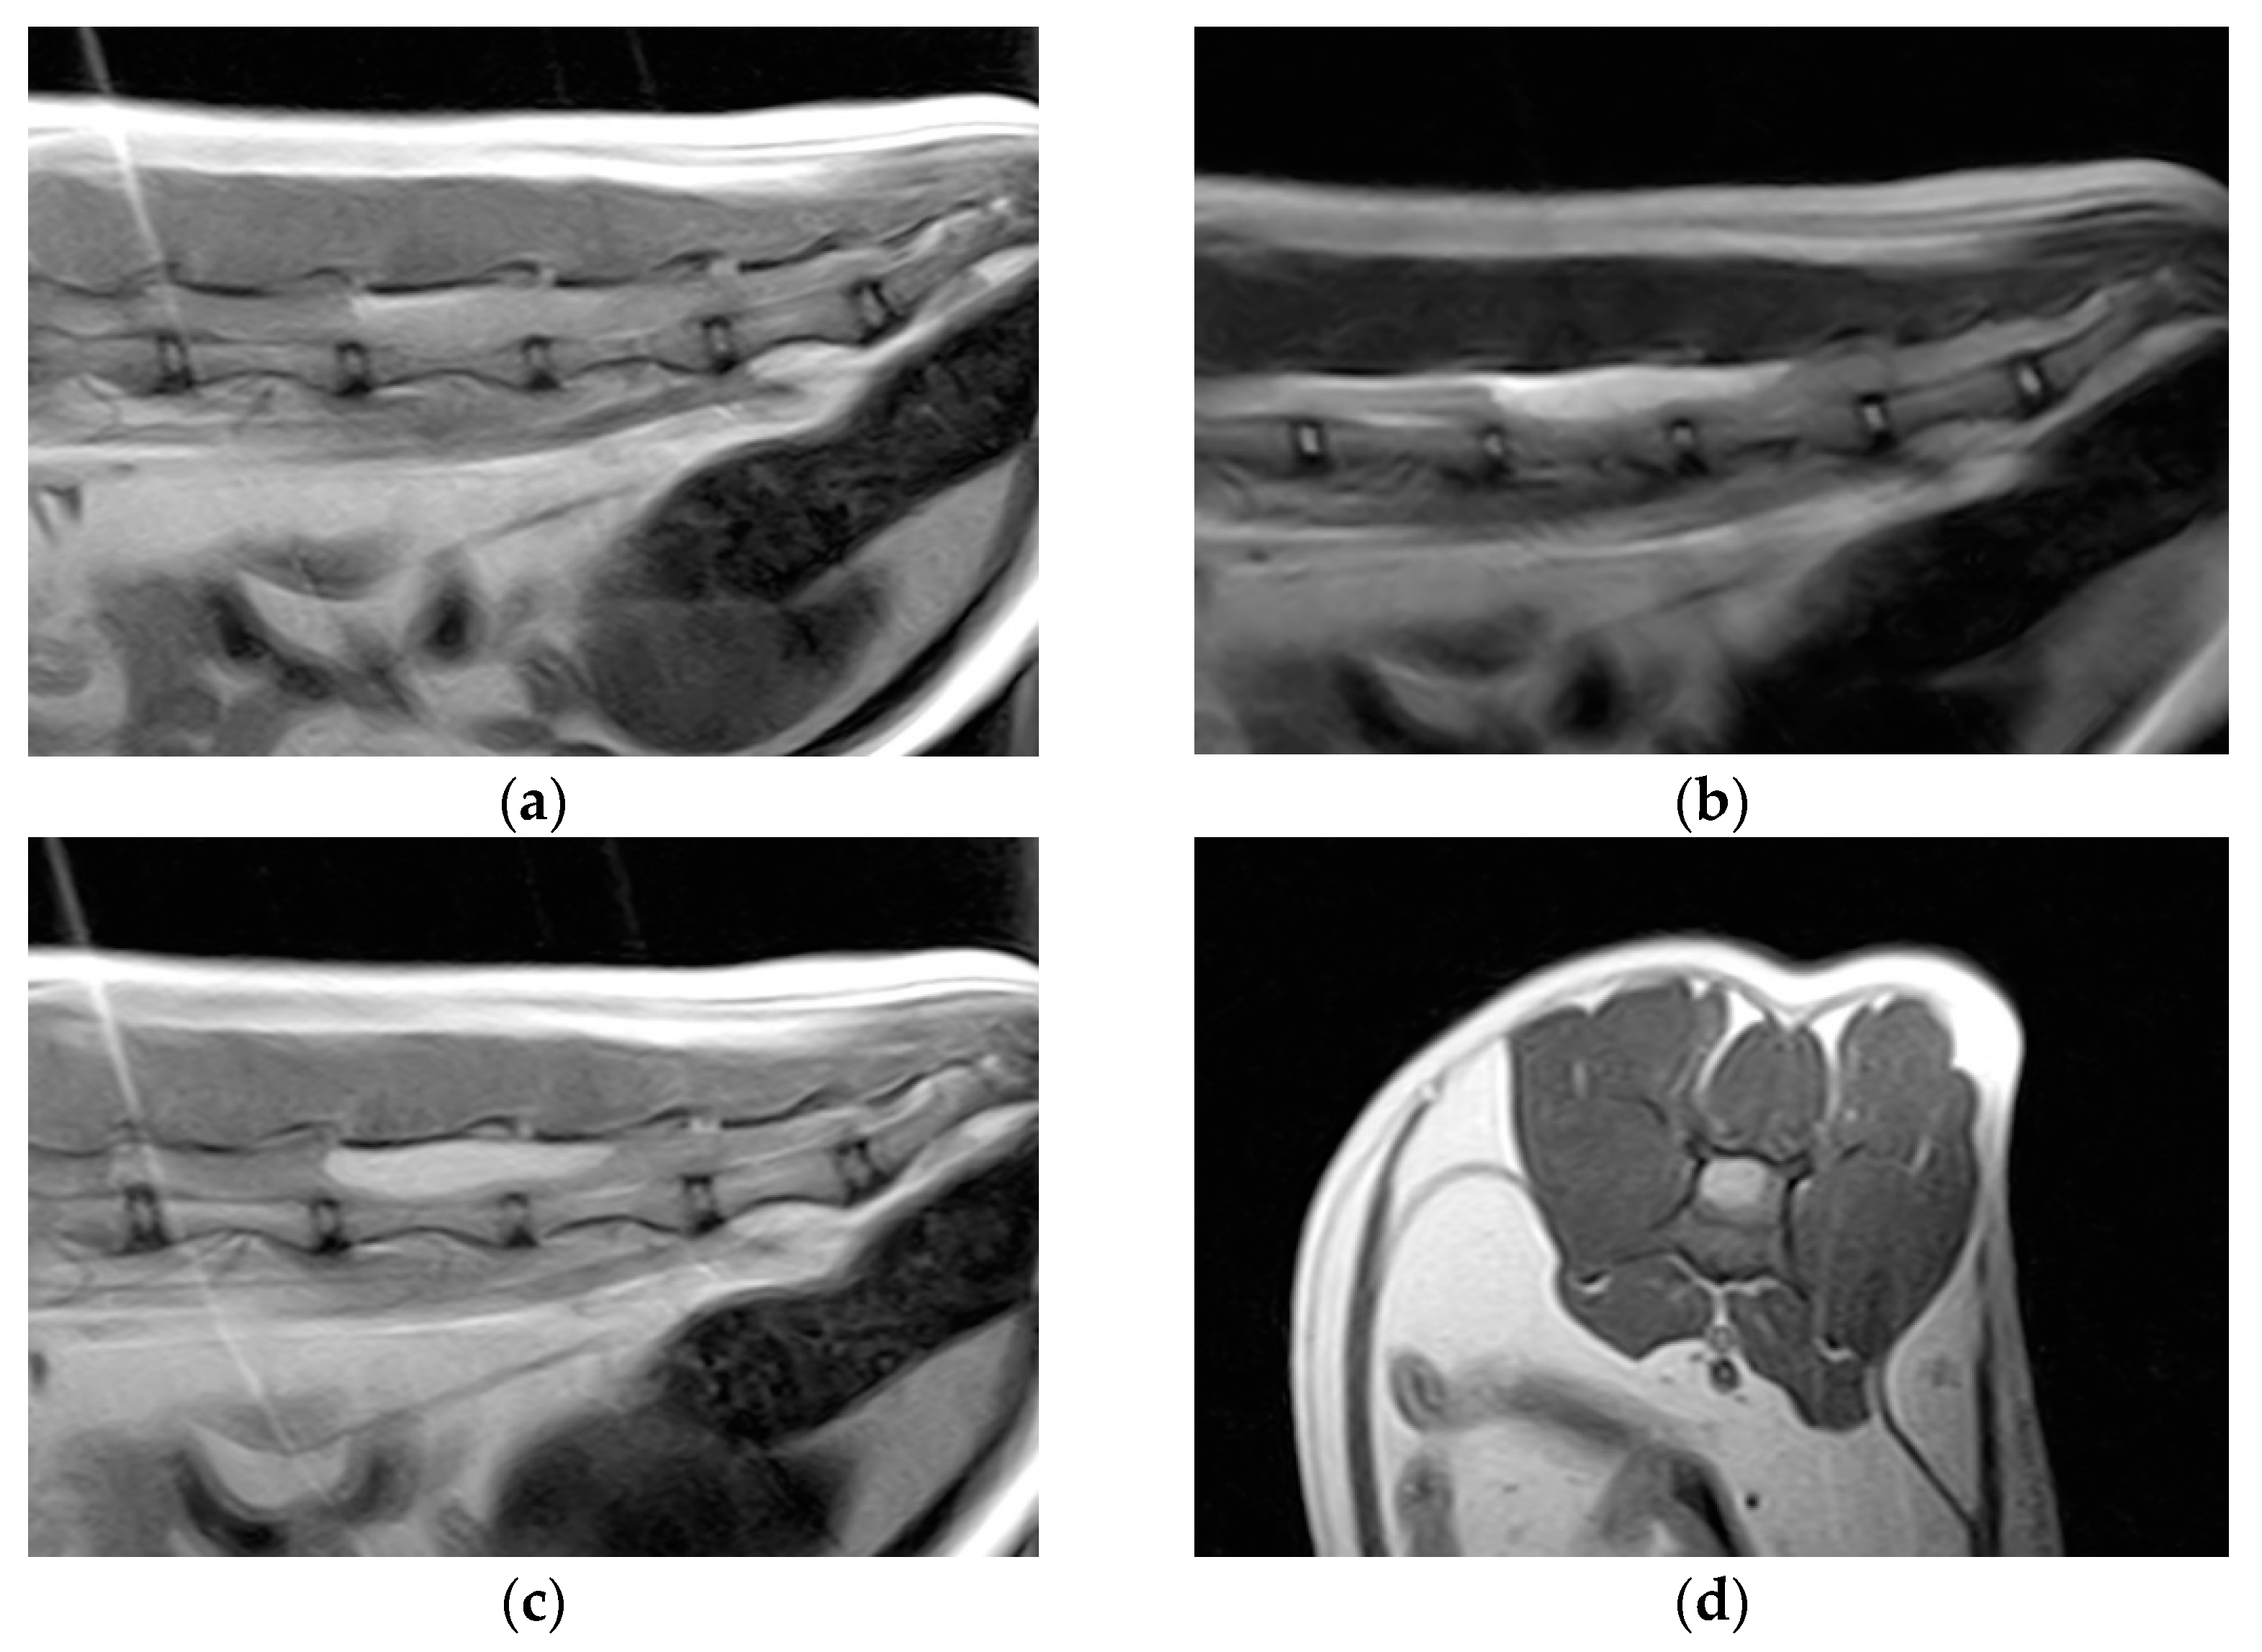

2. Case Description